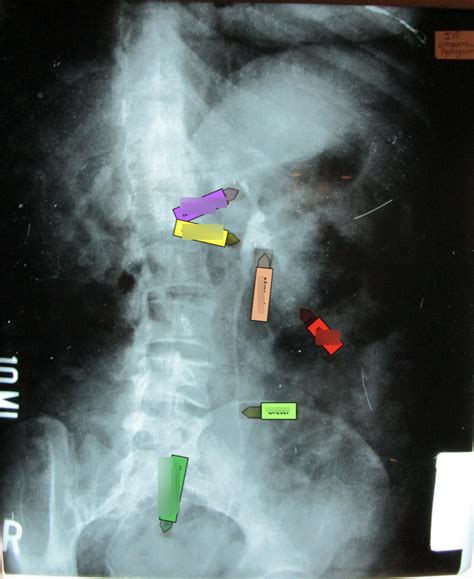

The Anatomy Unveiled: What IVP Shows Us

Now, let’s get into the really interesting stuff: the anatomy ! An IVP provides a detailed view of the urinary system’s structures. The key players here are the kidneys, ureters, and bladder, all working together to filter waste and produce urine. Think of it as a beautifully orchestrated team! The radiologist analyzes the images to assess the size, shape, and function of each of these parts.

The kidneys , those bean-shaped organs, are the workhorses of the urinary system. They filter waste from the blood and produce urine. An IVP allows us to see the kidneys’ internal structure, including the renal pelvis and calyces . The renal pelvis is the funnel-shaped part that collects urine before it flows into the ureter. The calyces are cup-like structures that collect urine from the kidney’s filtering units. An IVP can reveal if the kidneys are enlarged, if there are any obstructions (like kidney stones), or if there are any abnormalities in their shape or position. The radiologist carefully examines the renal parenchyma (the functional tissue of the kidney) for any signs of disease.

Ureters: The Urine Highways

The ureters are the tubes that transport urine from the kidneys to the bladder. On an IVP, we can see the ureters’ course as they descend from the kidneys. We can assess their width and look for any blockages, such as kidney stones, or compressions. The IVP allows us to observe peristaltic movement, the wavelike contractions that propel urine down the ureters. This is super important because any obstruction in the ureters can lead to a buildup of urine, potentially causing pain and kidney damage. This visualization is essential for making a diagnosis.

The bladder is the final stop in the urinary journey, acting as a storage tank for urine. On an IVP, we can see the bladder’s shape, size, and its ability to fill and empty. The IVP can help detect bladder tumors, diverticula (pouches), or other abnormalities. Observing the bladder’s function during the voiding phase is also crucial to identify any obstructions or problems with urine flow. The radiologist uses the images to evaluate how the bladder functions and to identify any possible issues.